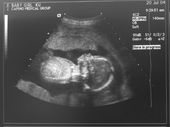

Ultrasounds

IT'S A GIRL!!! Here are the ultrasound scans. She is now 5-6" crown to rump (head to butt) My favorite pictures are of the foot and the one where she is sucking on her thumb.